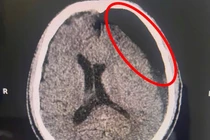

Sau khi tiếp nhận, bệnh viện đã kích hoạt quy trình báo động đỏ toàn viện, trẻ được các bác sĩ đã nhanh chóng xử trí hồi sức, cấp cứu suy hô hấp, cấp cứu ngừng tim, ngừng tuần hoàn, chăm sóc tích cực và thực hiện các cận lâm sàng. Kết quả cho thấy trẻ bị vỡ xương sọ phức tạp, kèm theo chảy máu và dập não phức tạp.

Các bác sĩ chuyên ngành ngoại thần kinh nhi của Bệnh viện Sản Nhi đã tiến hành phối hợp hội chẩn liên viện với chuyên gia ngoại thần kinh của Bệnh viện Đa khoa tỉnh; Trẻ được chẩn đoán bị xuất huyết nội sọ do chấn thương sọ não, tăng áp lực nội sọ, suy hô hấp và nhanh chóng được chuyển phòng mổ chỉ định mổ cấp cứu chấn thương sọ não.

Hình ảnh phim chụp chấn thương sọ não nặng - Ảnh BVCC